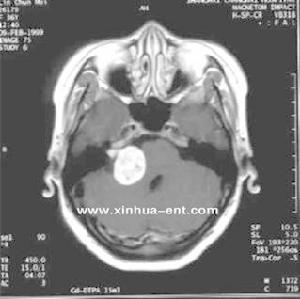

3.CT及MRI等檢查

CT檢查(1)激素治療:潑尼松(20~40mg)或地塞米松(1.5~4.5mg)口服火罐網1次/d,連續10~14天后逐漸減量應加服鉀鹽。